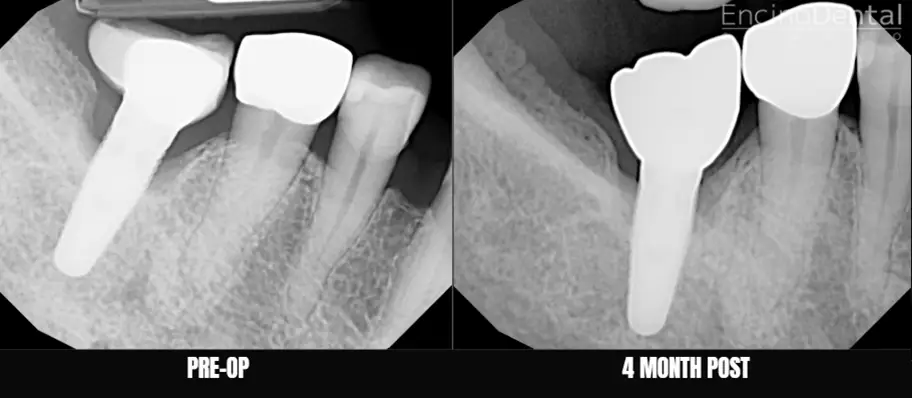

Before and After LAPIP at Encino Dental Studio